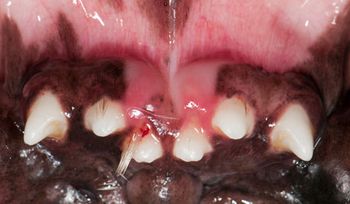

When hair becomes embedded in the oral cavities of your veterinary patients, it can cause inflammation and the destruction of periodontal attachment. Know where to look for it, how to treat it and how to keep it from recurring.